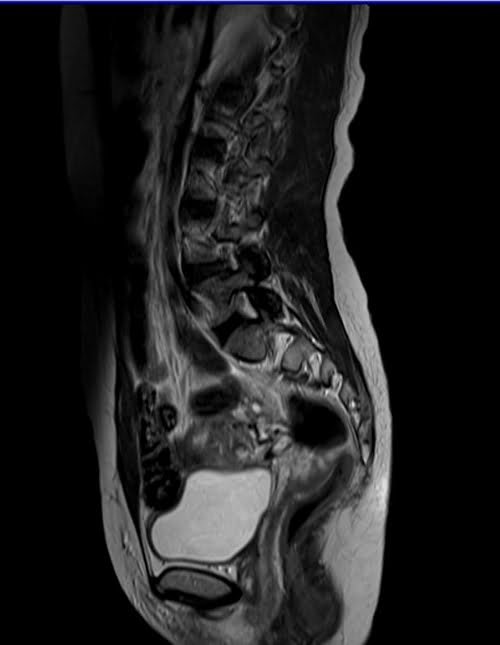

mri lumbosacral plexus sagittal t2 image 1 - MRI